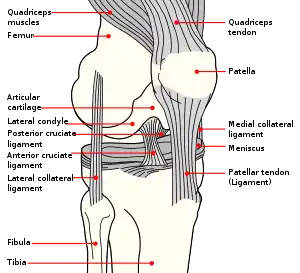

In humans and other primates, the knee joins the thigh with the leg and consists of two joints: one between the femur and tibia (tibiofemoral joint), and one between the femur and patella (patellofemoral joint).[1] It is the largest joint in the human body.[2] The knee is a modified hinge joint, which permits flexion and extension as well as slight internal and external rotation. The knee is vulnerable to injury and to the development of osteoarthritis.

It is often termed a compound joint having tibiofemoral and patellofemoral components.[3][4] (The fibular collateral ligament is often considered with tibiofemoral components.)[5]

The knee is a modified hinge joint, a type of synovial joint, which is composed of three functional compartments: the patellofemoral articulation, consisting of the patella, or "kneecap", and the patellar groove on the front of the femur through which it slides; and the medial and lateral tibiofemoral articulations linking the femur, or thigh bone, with the tibia, the main bone of the lower leg.[6] The joint is bathed in synovial fluid which is contained inside the synovial membrane called the joint capsule. The posterolateral corner of the knee is an area that has recently been the subject of renewed scrutiny and research.[7]

Articular bodies

The main articular bodies of the femur are its lateral and medial condyles. These diverge slightly distally and posteriorly, with the lateral condyle being wider in front than at the back while the medial condyle is of more constant width. [10]: 206 The radius of the condyles' curvature in the sagittal plane becomes smaller toward the back. This diminishing radius produces a series of involute midpoints (i.e. located on a spiral). The resulting series of transverse axes permit the sliding and rolling motion in the flexing knee while ensuring the collateral ligaments are sufficiently lax to permit the rotation associated with the curvature of the medial condyle about a vertical axis.[10]: 194–95

The pair of tibial condyles are separated by the intercondylar eminence[10]: 206 composed of a lateral and a medial tubercle.[10]: 202

The patella also serves an articular body, and its posterior surface is referred to as the trochlea of the knee.[11] It is inserted into the thin anterior wall of the joint capsule.[10]: 206 On its posterior surface is a lateral and a medial articular surface,[10]: 194 both of which communicate with the patellar surface which unites the two femoral condyles on the anterior side of the bone's distal end.[10]: 192

Menisci

The articular disks of the knee-joint are called menisci because they only partly divide the joint space.[10]: 26 These two disks, the medial meniscus and the lateral meniscus, consist of connective tissue with extensive collagen fibers containing cartilage-like cells. Strong fibers run along the menisci from one attachment to the other, while weaker radial fibers are interlaced with the former. The menisci are flattened at the center of the knee joint, fused with the synovial membrane laterally, and can move over the tibial surface. [10]: 208 [15] The upper and lower surfaces of the menisci are free. Each meniscus have anterior and posterior horns that meet in the intercondylar area of the tibia.[13]

Medial meniscus is bigger, less curved, and thinner. Its posterior horn is thicker (14mm) than the anterior horn (6mm).[13]

The lateral meniscus is smaller, more curved (nearly circular), and has more uniform thickness than medial meniscus (10mm). The lateral meniscus is less attached to the joint capsule, because its posterolateral surface is grooved by the popliteus tendon, separating the meniscus from the capsule. The popliteus tendon is not attached to the lateral meniscus.[13]

Ligaments

The ligaments surrounding the knee joint offer stability by limiting movements and, together with the menisci and several bursae, protect the articular capsule.[16]

Intracapsular

The knee is stabilized by a pair of cruciate ligaments. These ligaments are both extrasynovial, intracapsular ligaments.[17] The anterior cruciate ligament (ACL) stretches from the lateral condyle of femur to the anterior intercondylar area.[13] The ACL is critically important because it prevents the tibia from being pushed too far anterior relative to the femur.[13] It is often torn during twisting or bending of the knee.[18] The posterior cruciate ligament (PCL) stretches from medial condyle of femur to the posterior intercondylar area. This ligament prevents posterior displacement of the tibia relative to the femur.[13] Injury to this ligament is uncommon but can occur as a direct result of forced trauma to the ligament.

The transverse ligament stretches from the lateral meniscus to the medial meniscus. It passes in front of the menisci. It is divided into several strips in 10% of cases.[10]: 208 The two menisci are attached to each other anteriorly by the ligament.[19] The posterior (of Wrisberg) and anterior meniscofemoral ligaments (of Humphrey) stretch from the posterior horn of the lateral meniscus to the medial femoral condyle. They pass anterior and posterior to the posterior cruciate ligament respectively.[13][10]: 208 The meniscotibial ligaments (or "coronary") stretches from inferior edges of the menisci to the periphery of the tibial plateaus.

Extracapsular

The patellar ligament connects the patella to the tuberosity of the tibia. It is also occasionally called the patellar tendon because there is no definite separation between the quadriceps tendon (which surrounds the patella) and the area connecting the patella to the tibia. [20] This very strong ligament helps give the patella its mechanical leverage [21] and also functions as a cap for the condyles of the femur. Laterally and medially to the patellar ligament the lateral and medial retinacula connect fibers from the vasti lateralis and medialis muscles to the tibia. Some fibers from the iliotibial tract radiate into the lateral retinaculum and the medial retinaculum receives some transverse fibers arising on the medial femoral epicondyle.[10]: 206

The medial collateral ligament (MCL a.k.a. "tibial") stretches from the medial epicondyle of the femur to the medial tibial condyle. It is composed of three groups of fibers, one stretching between the two bones, and two fused with the medial meniscus. The MCL is partly covered by the pes anserinus and the tendon of the semimembranosus passes under it.[10]: 206 It protects the medial side of the knee from being bent open by a stress applied to the lateral side of the knee (a valgus force).[10]: 206

The lateral collateral ligament (LCL a.k.a. "fibular") stretches from the lateral epicondyle of the femur to the head of fibula. It is separate from both the joint capsule and the lateral meniscus.[10]: 206 It protects the lateral side from an inside bending force (a varus force). The anterolateral ligament (ALL) is situated in front of the LCL.

Lastly, there are two ligaments on the dorsal side of the knee. The oblique popliteal ligament is a radiation of the tendon of the semimembranosus on the medial side, from where it is direct laterally and proximally. The arcuate popliteal ligament originates on the apex of the head of the fibula to stretch proximally, crosses the tendon of the popliteus muscle, and passes into the capsule.[10]: 206